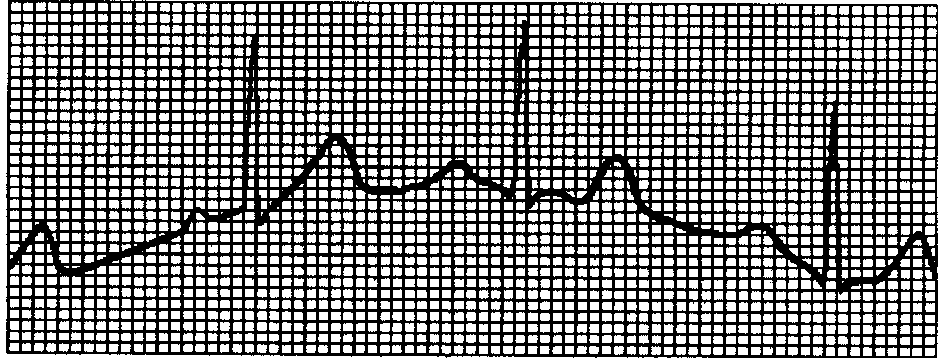

4.2 有肌电干扰

4.3 基线不稳

| 基线有毛刺 | 交流电干扰大 | 改善环境;若是钢铁床,需要更换;采集设备与其他大功率设备或电源距离太近 |

| 肌电干扰大 | 让病人放松、室内温度调整到16℃以上 | |

| 波形不规律,起伏大,打直线 | 电极导电性不好、电极与皮肤接触不良、导联线与主机的插头部分不够紧、导联线与电极接触不良 | 用的酒精要良好、用酒精清洗电极板及电极板下的皮肤 |

| 基线不稳 | 病人有移动 | 让病人安静 |